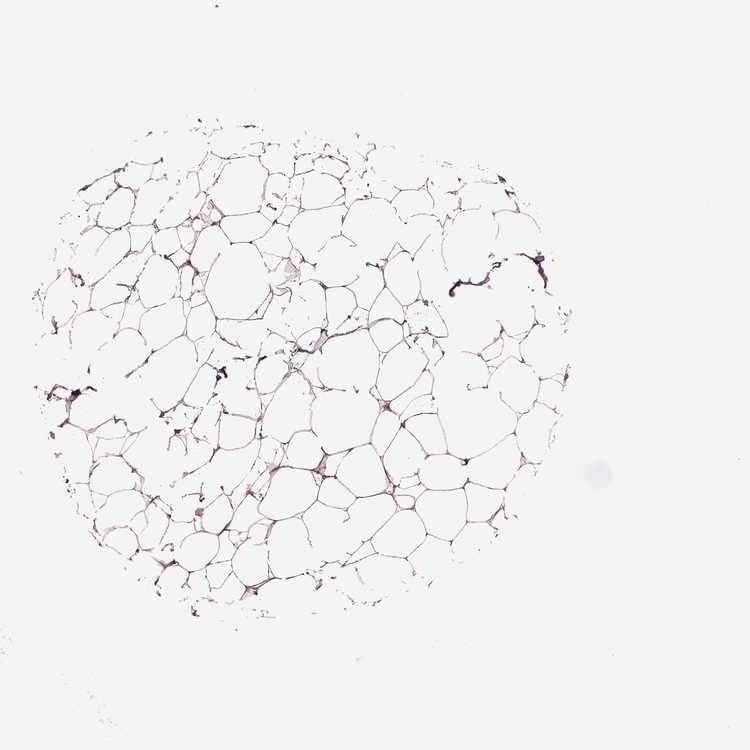

BREAST - Antibody stainingi

Antibody staining in the annotated cell types in the current human tissue is reported as not detected, low, medium, or high, based on conventional immunohistochemistry profiling in selected tissues. This score is based on the combination of the staining intensity and fraction of stained cells.

Each image is clickable and will lead to virtual microscopy that enables deeper exploration of all samples and also displays staining intensity scores, fraction scores and subcellular localization as well as patient and tissue information for each sample.

Antibody HPA072613

Adipocytes Medium

Glandular cells High

Myoepithelial cells Not detected